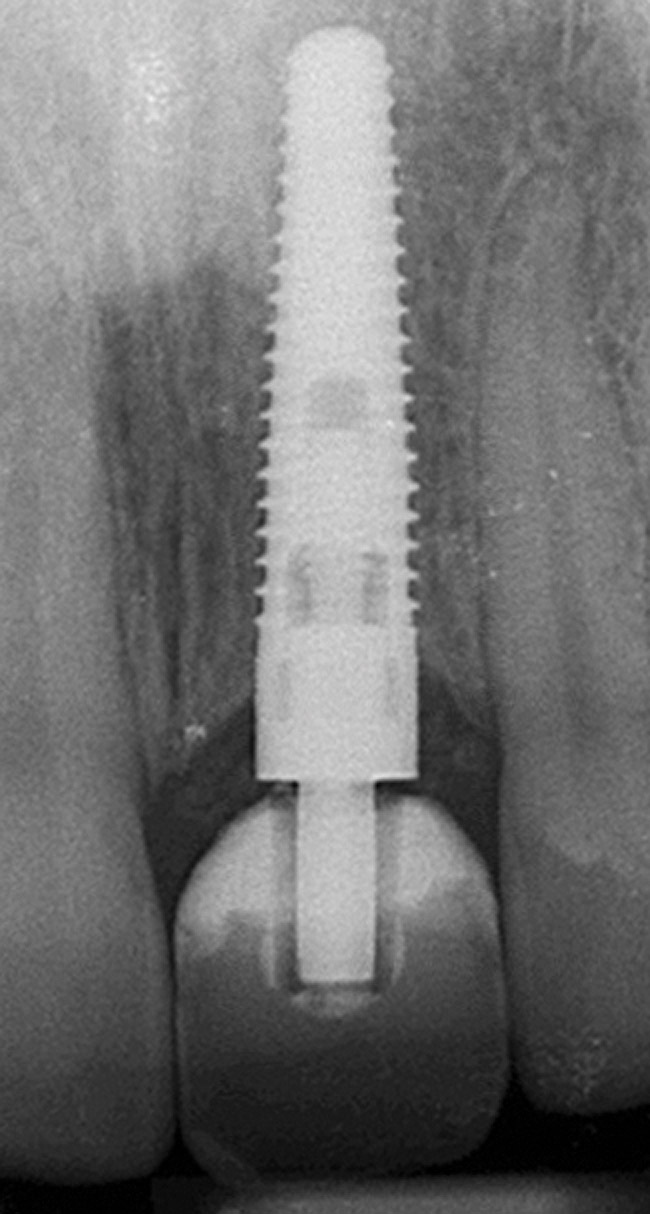

Figure 10  Tooth No. 9, pretreatment, showing Ellis Class III crown fracture; completed endodontic treatment, provisional post and core—periapical views.

Figure 10

Emergency endodontic treatment had been completed to manage the traumatically exposed root canal; Figure 10 shows the pre-treatment (Ellis Class III crown fracture) and post–endodontic-treatment periapical views of tooth No. 9. The restorative dentist temporarily cemented a glass-reinforced fiber post and used a fiber-reinforced composite core buildup material as an immediate provisional. Several weeks later, a provisional bis-acryl temporary crown on No. 9 was cemented on a larger-diameter glass-reinforced fiber post retaining a new fiber-reinforced composite core. Figure 11 shows the final feldspathic porcelain crown placed by the restorative dentist. During the fabrication and cementation of this crown, the remaining root appeared intact and the tooth was asymptomatic.